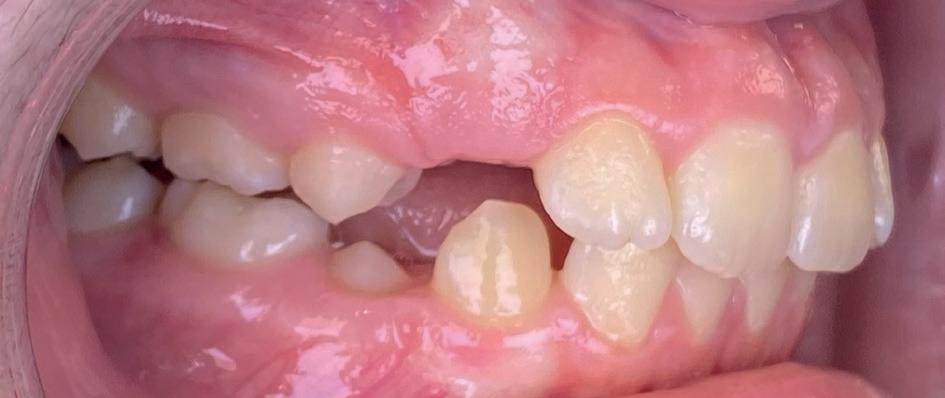

Casus: Blix – Ruimte creëren zonder extracties met D-gainer en Damon Ultima Blix (10 jaar) presenteerde zich met een klasse II-occlusie, smalle boven- en onderkaak en ruimtegebrek voor de doorbraak van de hoektanden en premolaren. Hoewel haar gezicht in balans was, zou zonder behandeling het gebrek aan ruimte toenemen en de diepe beet verder verergeren.

Behandeling in twee fasen

1. D-gainer & verbreding

Om extracties te voorkomen, werd gestart met een D-gainer. Dit is een methode met slotjes en veertjes waarmee de molaren gecontroleerd naar achteren worden verplaatst. Tegelijkertijd werd de tandboog verbreed – zonder buitenboordbeugel.

• Doel: ruimte creëren voor de hoektanden (13/23) zonder premolaren te verwijderen

• Duur: ongeveer 6 maanden

2. Vaste beugel (Damon Ultima)

Na voldoende ruimte werd gestart met de volledige vaste beugel in boven- en onderkaak. Hiermee werden de tandbogen uitgevlakt, de scheefstand gecorrigeerd en de tandbogen verbreed – met behoud van het natuurlijke profiel.

Resultaat

• Klasse I-occlusie

• Harmonieuze lachlijn en verbrede tandbogen

• Geen extracties

• Profiel en gezichtsbalans behouden

Retentie: Vaste spalk boven én onder, aangevuld met een nachtbeugel

“Door ruimte te creëren met een D-gainer in plaats van tanden te trekken, blijft het profiel natuurlijk en ontstaat een bredere, stabiele tandboog.”

voor